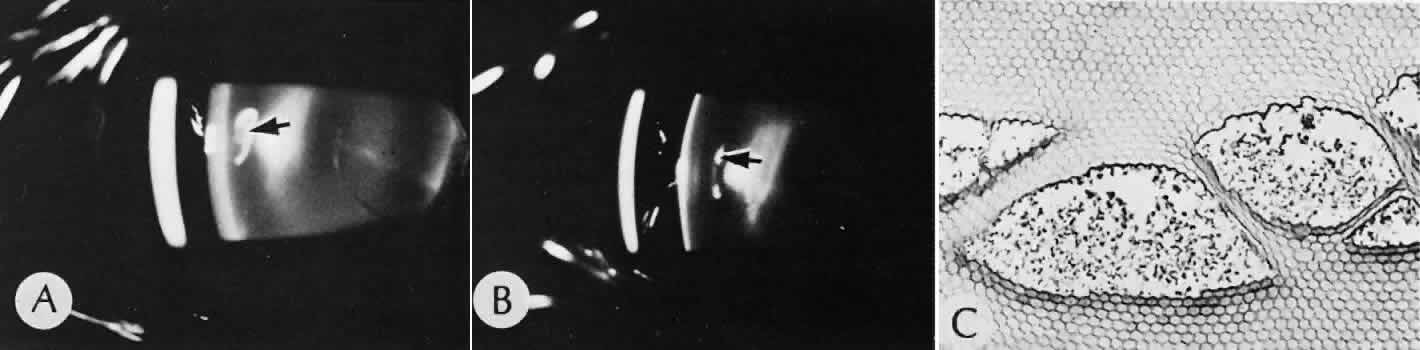

Cyclocryotherapy, cyclodiathermy (Fig. 20), and therapeutic ultrasonography apply energy directly to the pars plicata and cause lysis of the ciliary muscle and occlusion of the vascular supply, leading to extensive necrosis and scarring. Pressure lowering is accomplished by a reduction of aqueous production. Heat applied to the sclera may cause necrosis and localized scleral thinning. Cold applied to the sclera, unless extreme, does not cause any clinical or histologic changes.

Fig. 20. Cyclodiathermy treatment of the ciliary body to control glaucoma. A. Gross photograph illustrates extensive areas of depigmentation mainly in the region of the pars plana (arrows) rather than the pars plicata. B. Light micrograph of the region of the pars plana illustrates an extensive area of tissue degeneration of the pars plana (between arrows) in the late postoperative course. C. Light micrograph of the destructive effects of cyclocryotherapy also in the region of the pars plana and pars plicata. The ciliary epithelium in the early postoperative period is necrotic and cystic. (Hematoxin-eosin stain; A, × 8; B, × 16.)

Cyclodialysis (Fig. 21) creates a cleft between the sclera and the longitudinal muscle of the ciliary body. Aqueous passes directly from the anterior chamber into the suprachoroidal space. Histologically, the longitudinal muscle of the ciliary body is disinserted from the scleral spur. Diaphanous tissue often is present in the suprachoroidal space along the route of filtration. The presence of this tissue differentiates the surgical site from artifactual disinsertion of the ciliary body, which is a common artifact of ocular tissue preparation.

Fig. 21. Light micrograph of cyclodialysis. The region of the surgical cleft between the longitudinal muscle of the ciliary body and the sclera (arrow) is filled with delicate fibrous tissue. Note the posterior location of the anterior face of the ciliary body and the angle recesses in relationship to the scleral spur (S).